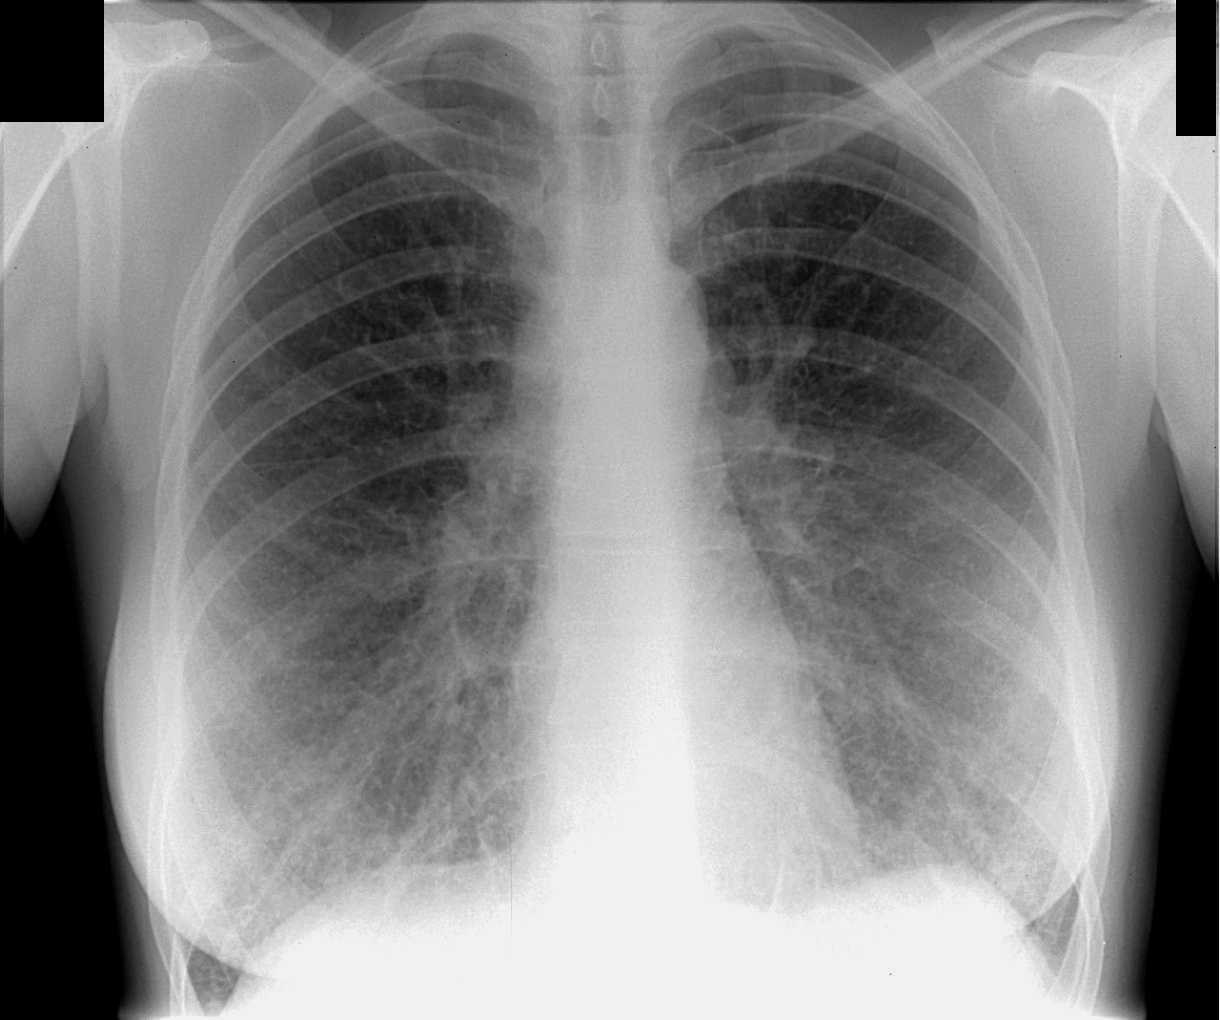

smalltownboy>> классная фотка. взрывчатки не заметно.

Дем> Ну да, а что полиэтиленовая плёнка менее прозрачна чем металл - никого не напрягло...

Это была флюрография:

Негатив/позитив - какая кому разница..